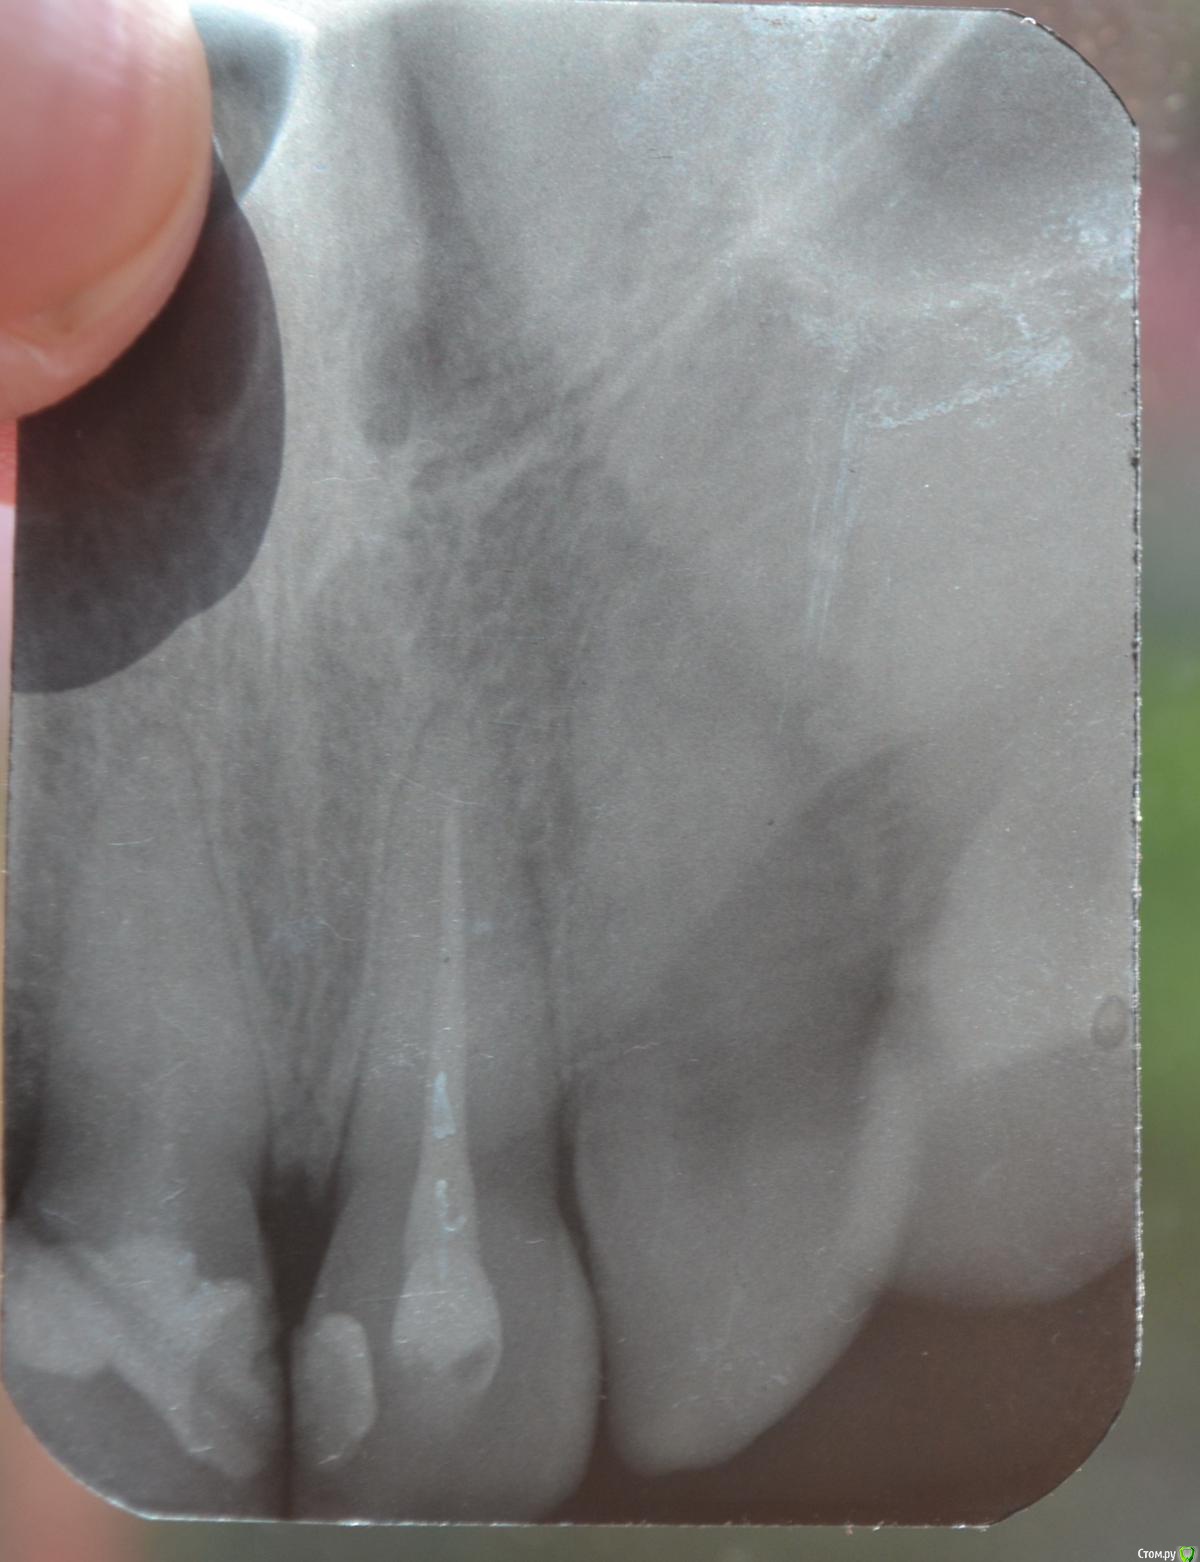

Llllll Опубликовано 16 июля, 2015 Автор Поделиться Опубликовано 16 июля, 2015 Сегодня делали рентген еще раз, и увидели на 1 зубе справа (тот, который болит) на самой верхушке корня кусочек инструмента. Рентгена нету, так как его на компьютере только смотрели. Сказали что достать его нельзя. Что делать? Ссылка на комментарий

Llllll Опубликовано 27 июля, 2015 Автор Поделиться Опубликовано 27 июля, 2015 Вот еще делали рентген с иголкой в зубе. Ссылка на комментарий